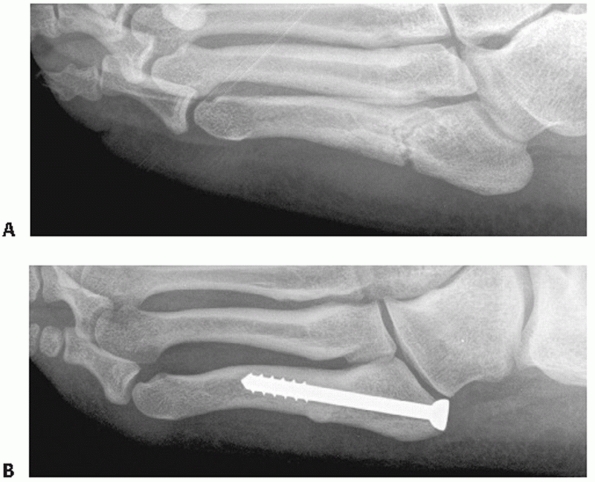

strength of individual ligaments across many of these joints. The

important characteristics to note are (a) the plantar ligaments are

significantly stronger than the dorsal ligaments, (b) the multiple

ligaments overlap among the joints of the lesser four tarsometatarsal

joints, and (c) the Lisfranc ligament, which is the largest and

strongest ligament of this joint complex, represents the only

ligamentous support between the medial leg and the middle and lateral

legs in the forefoot. The Lisfranc ligament originates from the plantar

lateral aspect of the medial cuneiform just below the plantar extent of

the second tarsometatarsal joint and inserts on the plantar and medial

aspect of the second metatarsal base. At best it is an indirect link

between the first and second metatarsals. There is no interligamentous

connection between the first and second metatarsal.

are important for management are stability and associated fracture

management. Extra-articular fractures, which appear with these

injuries, should be treated as described elsewhere in this text to

preserve that structure’s role in foot function. Intra-articular

fractures of the tarsometatarsal joints should be handled in the

context of the treatment of the joint complex.

with metatarsal motion, and tenderness to palpation but fail to exhibit

any instability should be considered a sprain. In addition to the

normal concept of rest, ice, compression, and elevation (RICE) for

treating sprains, the need for immobilization is important. These

injuries can be severely debilitating and require a long recovery

period.24,76

Nondisplaced ligamentous injuries with or without small plantar

avulsion fractures of the metatarsal or tarsal bones should be placed

in a well-molded short-leg walking cast (Table 60-5).

Initially, the patient is kept non-weight bearing with crutches and

only permitted to bear weight as comfort allows. Once full weight

bearing can be accomplished in a cast, the patient is tested for